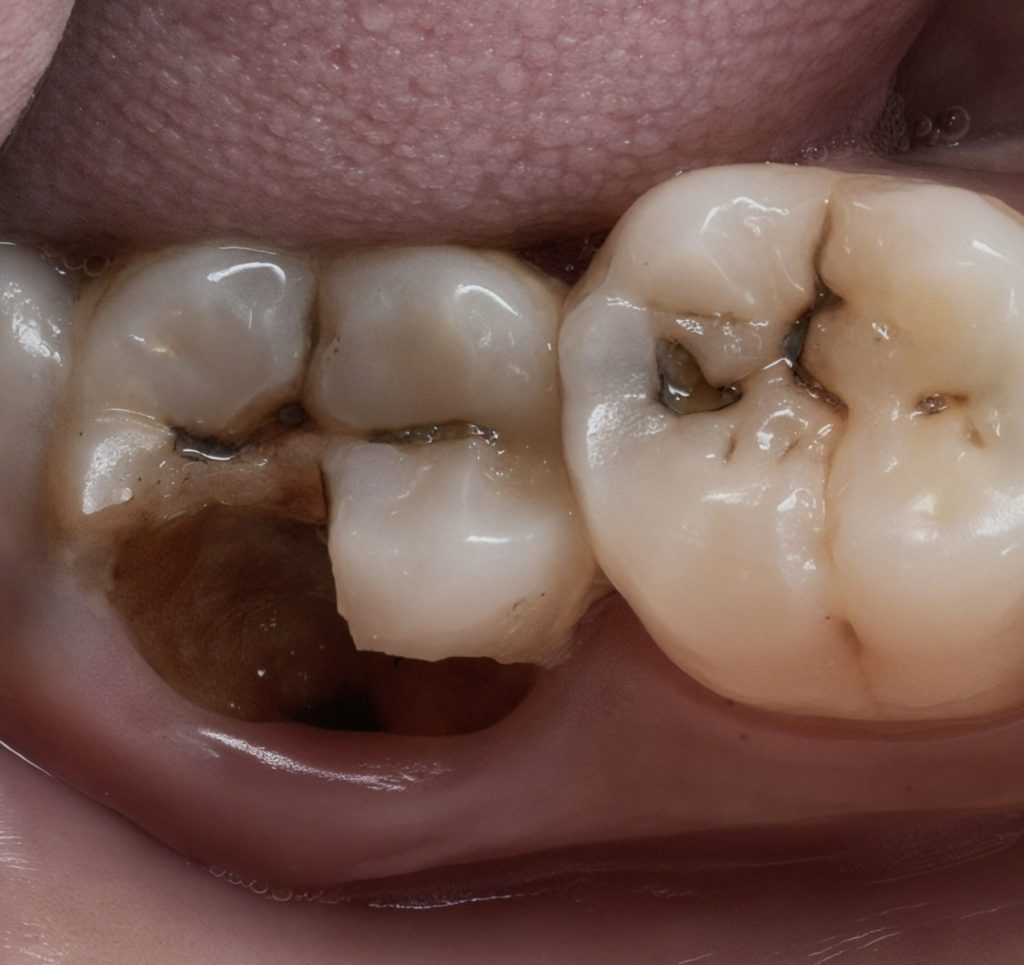

Clinical and radiographic evaluation showed a large Class V lesion extending below the CEJ with pulpal involvement and secondary dentin sclerosis (Fig 1 & 2).

1️⃣ Pre-operative view showing deep Class V caries

2️⃣ Pre-op radiograph